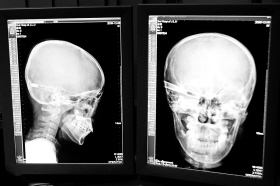

在接受x光檢查的小沖

“還是先做個X光透視,看一下箭桿到底有多深!毖劭漆t(yī)生緊急趕到CT室查看,和放射科的幾位醫(yī)生共同研究后,決定先讓小沖做X光透視。

“如果再用點力,就從后腦穿出來了!”由于小沖無法移動,醫(yī)生拿來移動插座,將透視的光板放在小沖的移動病床上,透視后讓在場的醫(yī)生都吃了一驚:箭桿直接穿過了大腦和小腦,箭尖兒直抵后顱骨,足足有10余厘米。